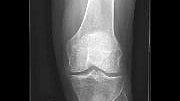

Knee replacement surgery in the morning, and back home that evening? Many patients are surprised to learn it is an option. Forgoing a night in the hospital has become increasingly common, and improvements in knee replacement technology, surgical technique and pain management make it possible, says Martin W. Roche, MD, an orthopedic surgeon and director of joint replacement at HSS Florida in West Palm Beach.

Dr. Roche points to advances over the past five years or so that benefit patients and can lead to a faster recovery: a CT scan before surgery to create a 3D model of the patient’s knee to plan a highly personalized procedure; the use of surgical robotics and sensors that allow for a high degree of precision and accuracy; less invasive, muscle-sparing surgery performed with smaller incisions; and a program called “pre-habilitation,” in which patients begin physical therapy to get stronger prior to knee replacement.